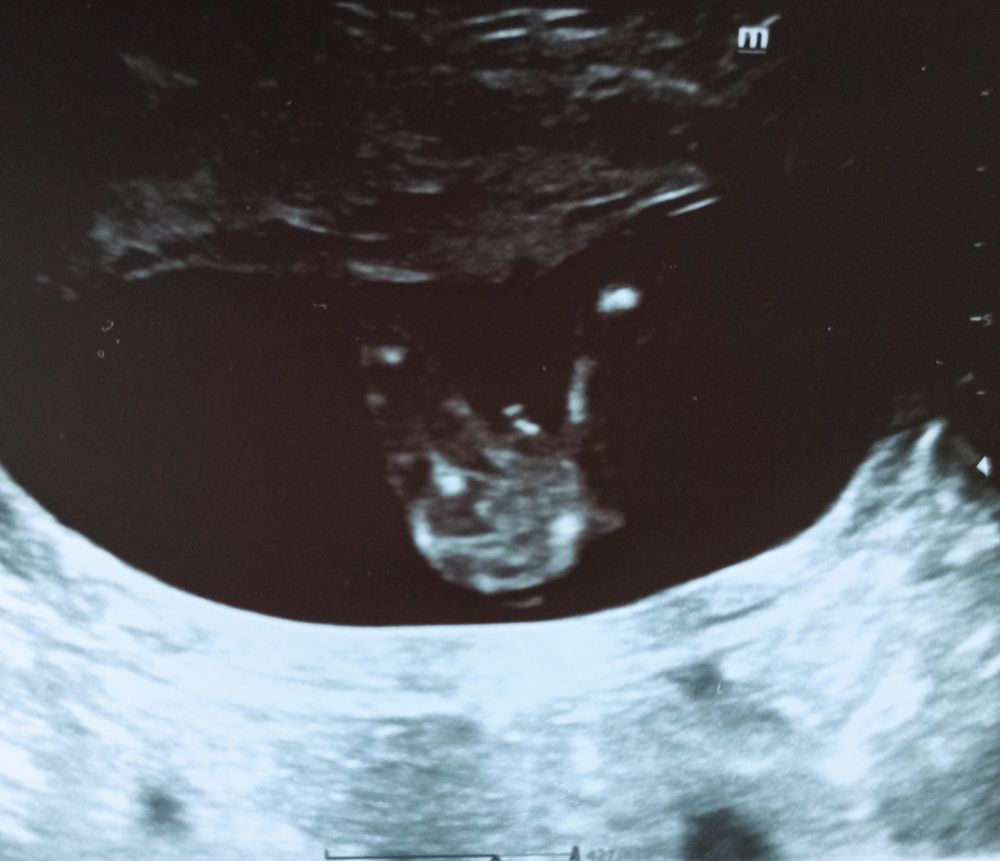

УЗИ в 16+3❤🤞🤞🤞

Единственное, что смутило, что костная часть спинки носа маловата - 3,3 мм на сроке 16 недель и 3 дня ( норма в 16-17 недель - от 3,6 мм). Я думаю, это не критично и НИПТ развеет все сомнения. Остальное всё в норме, соответствует сроку. Вес сыночка 166 грамм.

На фото открыл глазки:

Во - вторых, сегодня по УЗИ в 16+3 носовая кость маловата - 3,3 мм ( норма в 16-17 недель от 3,6 мм);